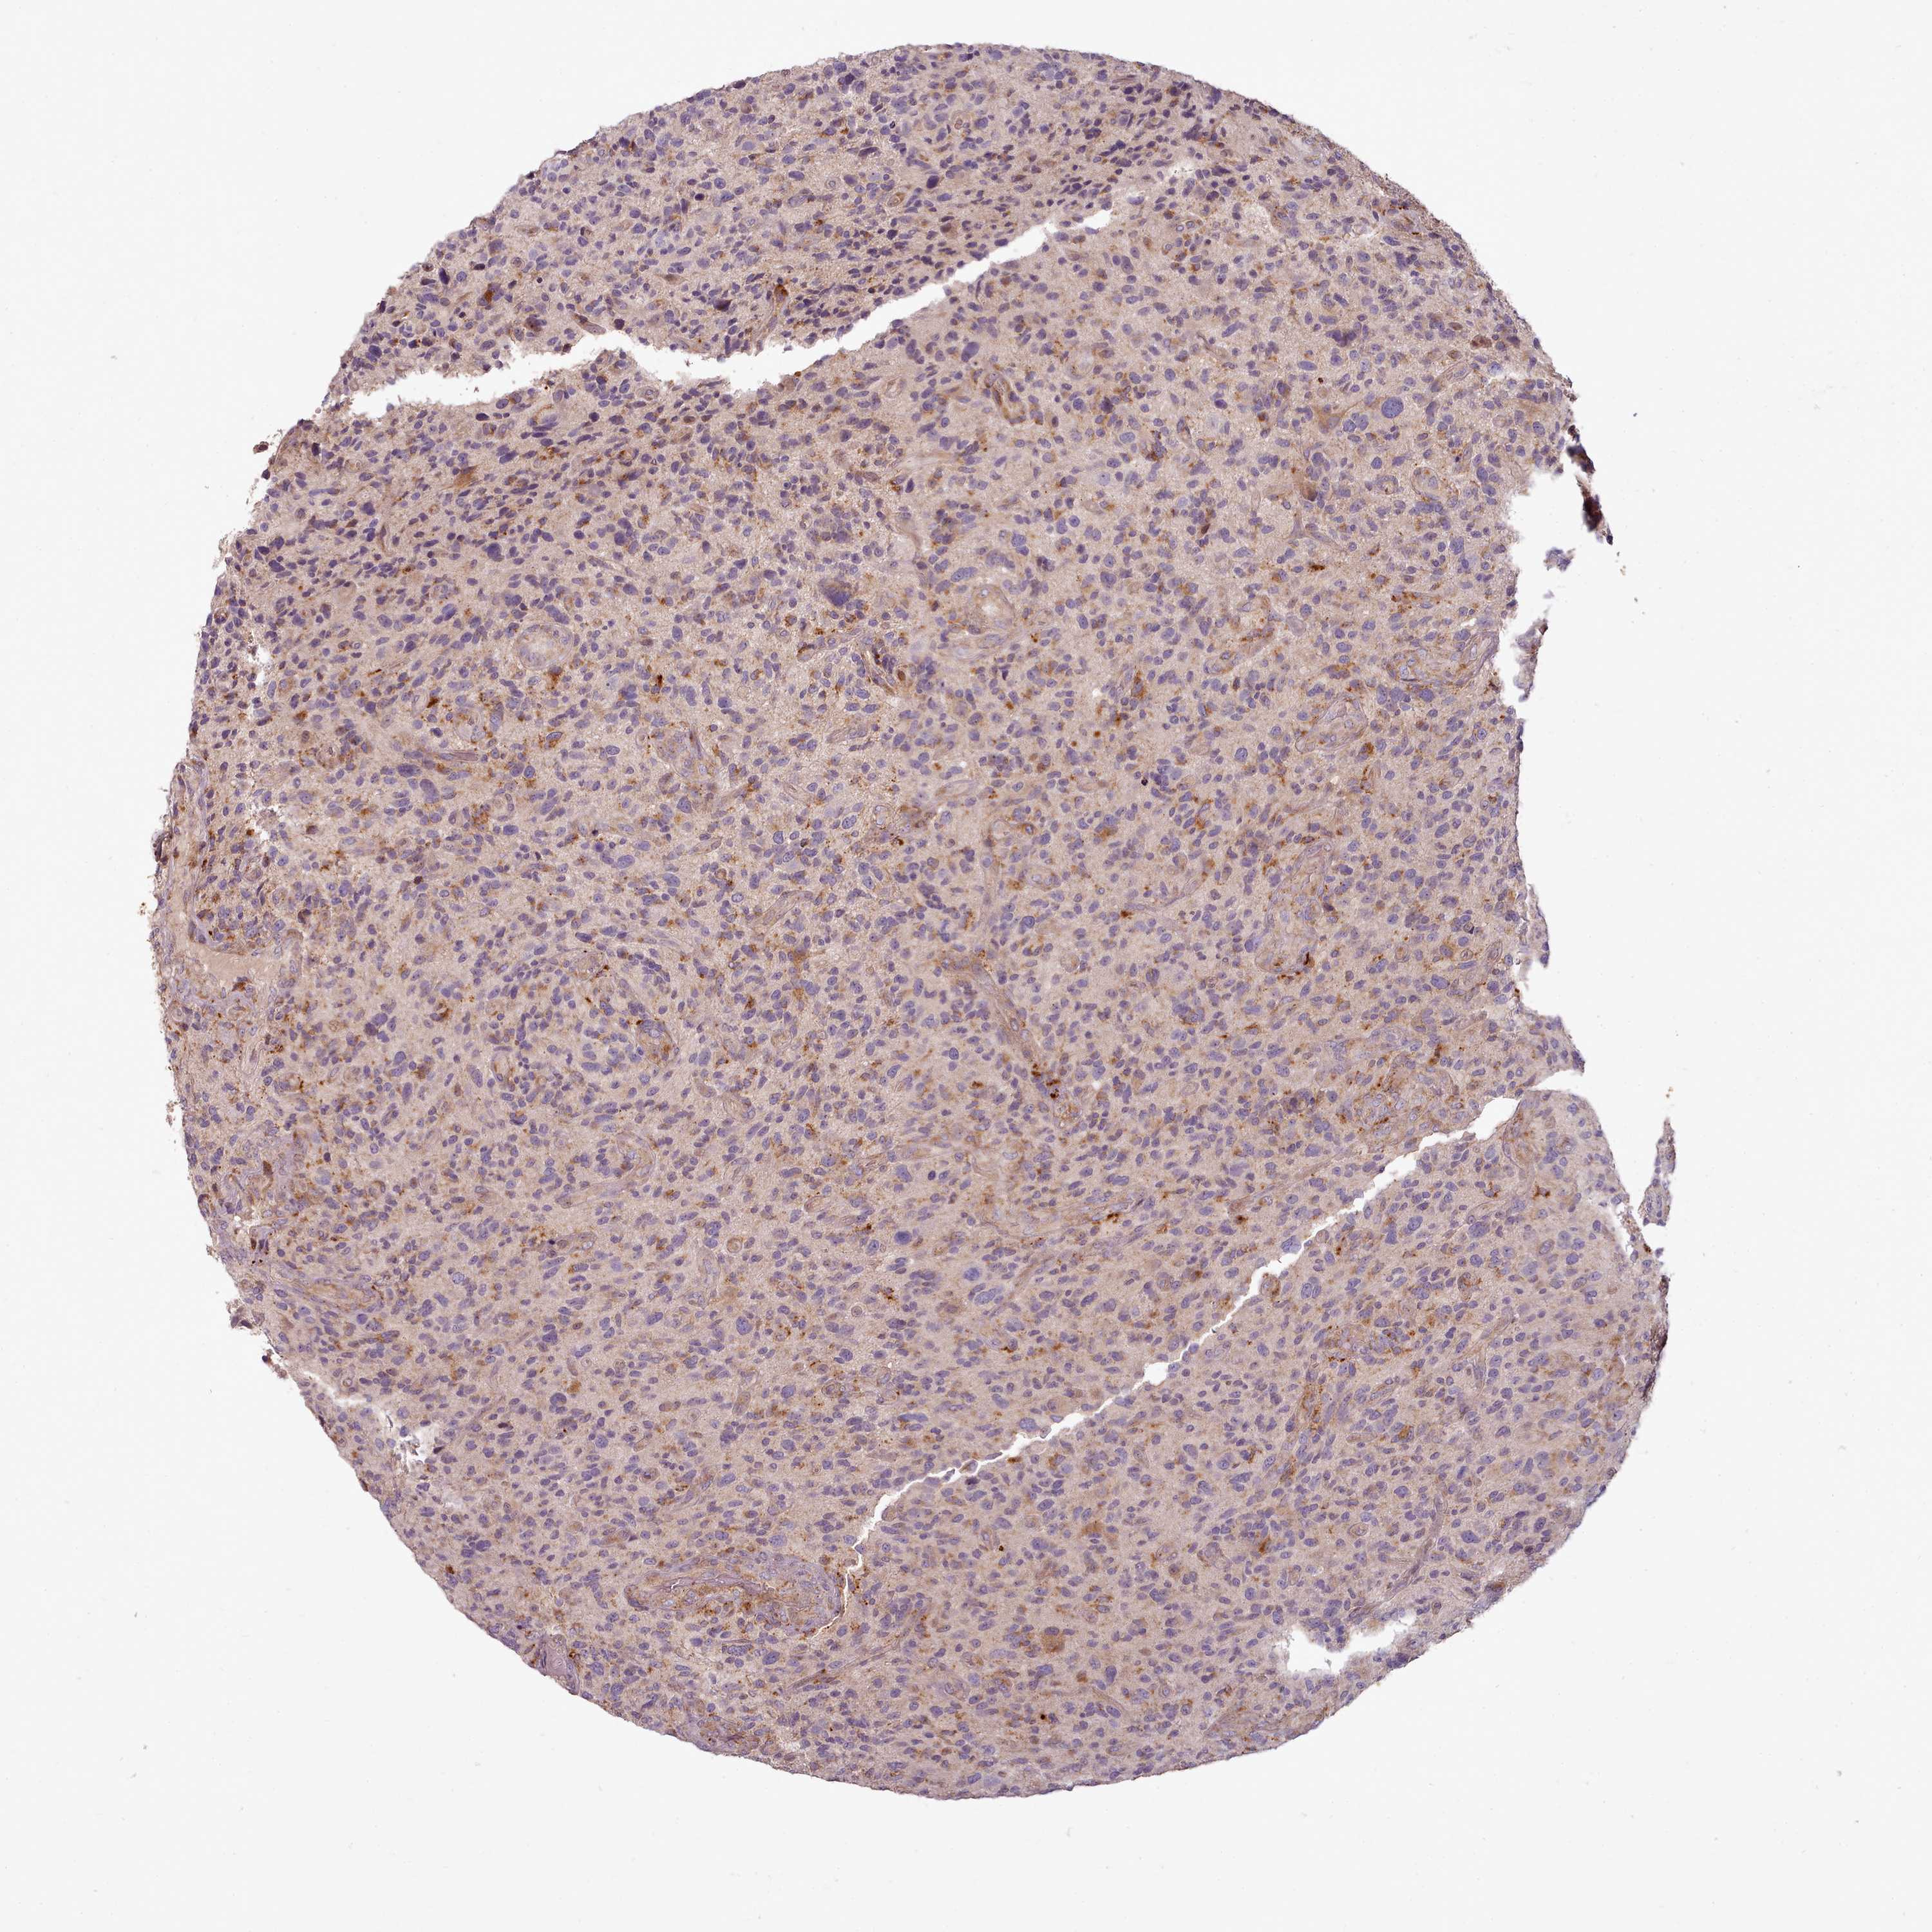

GLIOMA - Protein expressioni

A mouse-over function shows sample information and annotation data. Click on an image to view it in a full screen mode. Samples can be filtered based on level of antibody staining by selecting one or several of the following categories: high, medium, low and not detected. The assay and annotation is described here.

Note that samples used for immunohistochemistry by the Human Protein Atlas do not correspond to samples in the TCGA dataset.

Antibody stainingi

Antibody staining in the annotated cell types in the current human tissue is reported as not detected, low, medium, or high, based on conventional immunohistochemistry profiling in selected tissues. This score is based on the combination of the staining intensity and fraction of stained cells.

Each image is clickable and will lead to virtual microscopy that enables deeper exploration of all samples and also displays staining intensity scores, fraction scores and subcellular localization as well as patient and tissue information for each sample.

Antibody HPA038604

Antibody CAB025607

Staining

High

Medium

Low

Not detected

Intensity

Strong

Moderate

Weak

Negative

Quantity

>75%

75%-25%

<25%

None

Location

Nuclear

Cytoplasmic/membranous

Cytoplasmic/membranous,nuclear

Glioma, malignant, High grade

Glioma, malignant, Low grade